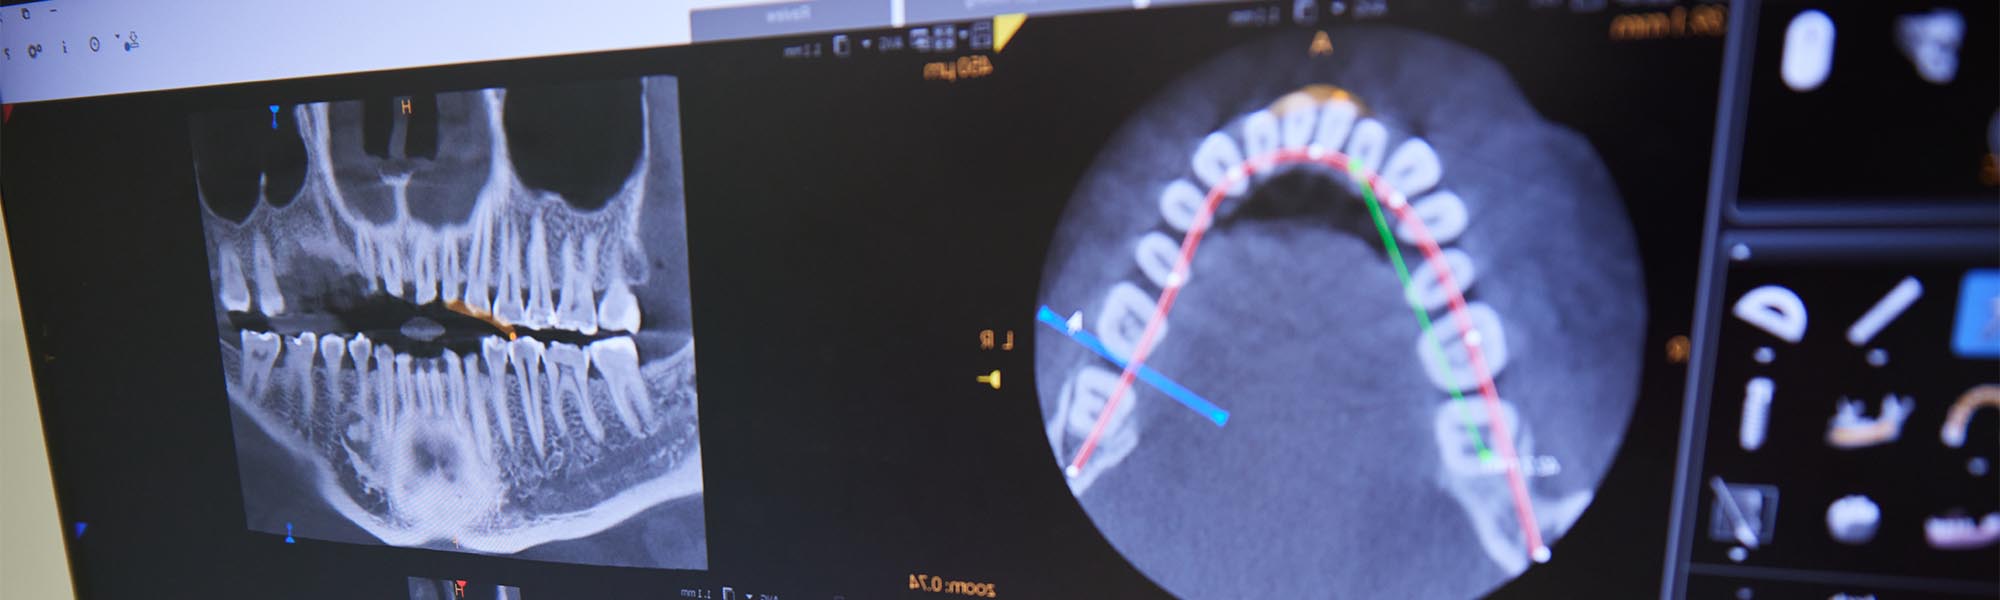

Digital X-Rays

The team at Dentists of Torrance views digital x-rays as one of the best advancements in dental technology.

With digital imagery, we can enlarge images, change the contrast, and improve sharpness – all of which contributes to more accurate diagnoses.

Another reason we’re fans of this technology is that digital x-rays produce up to 90% less radiation than traditional film x-rays.